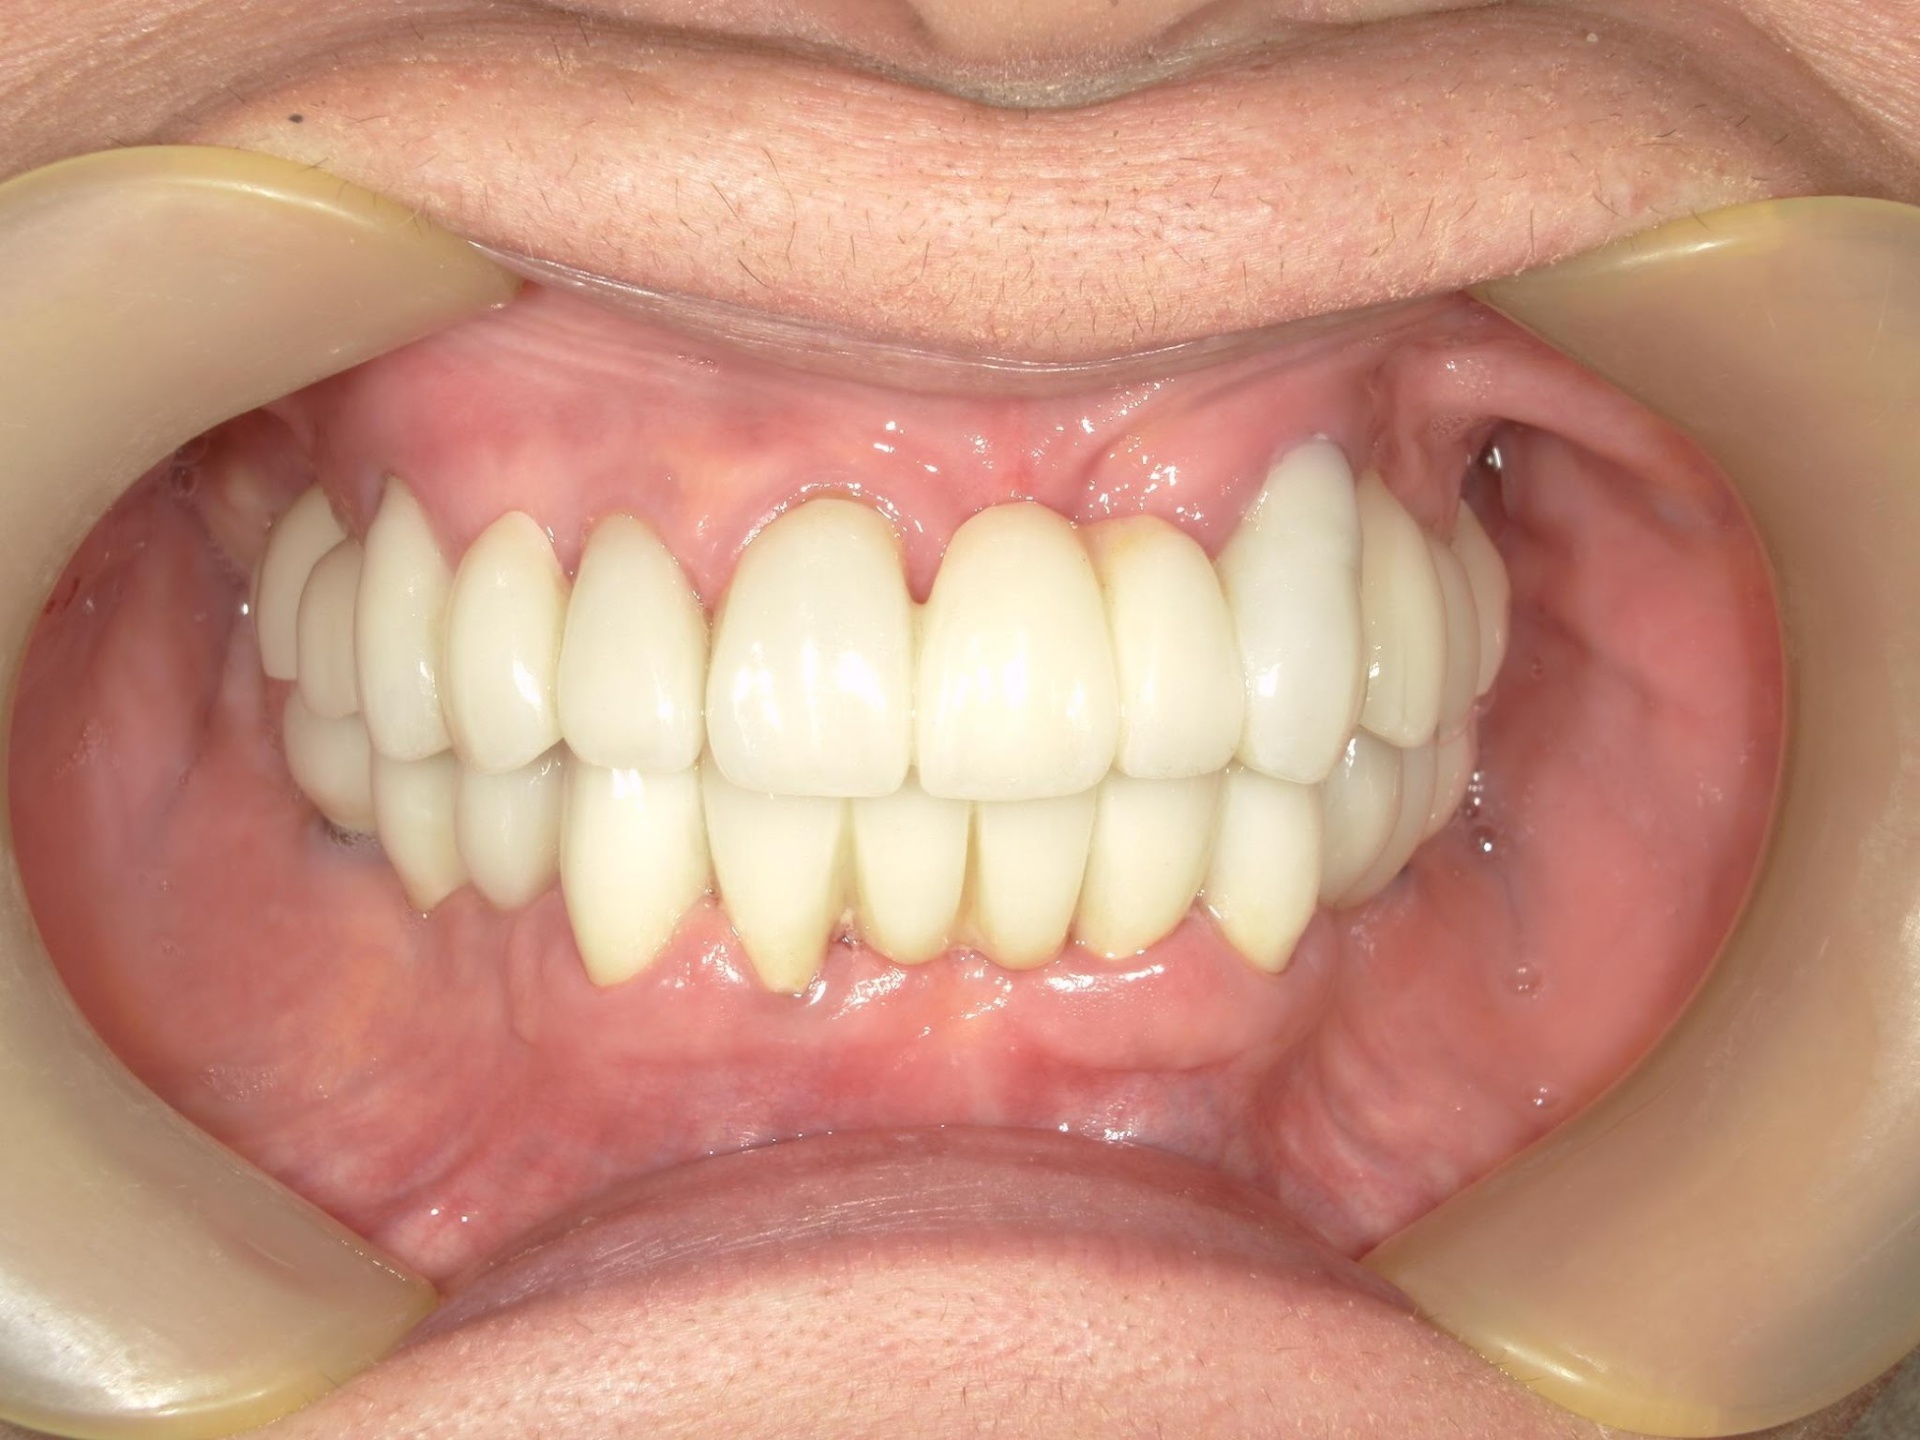

ここまで回復できる可能性があります

見た目だけでなく、しっかり噛める状態へ

Before

After

この症例では、単純に歯を入れるのではなく、

噛み合わせと力のバランスを再設計しています。

また、必要な場所にのみインプラントを用いることで、

残っている歯をできるだけ生かす治療設計としています。

その結果、見た目だけでなく、

長く安定して噛める状態を実現しています。